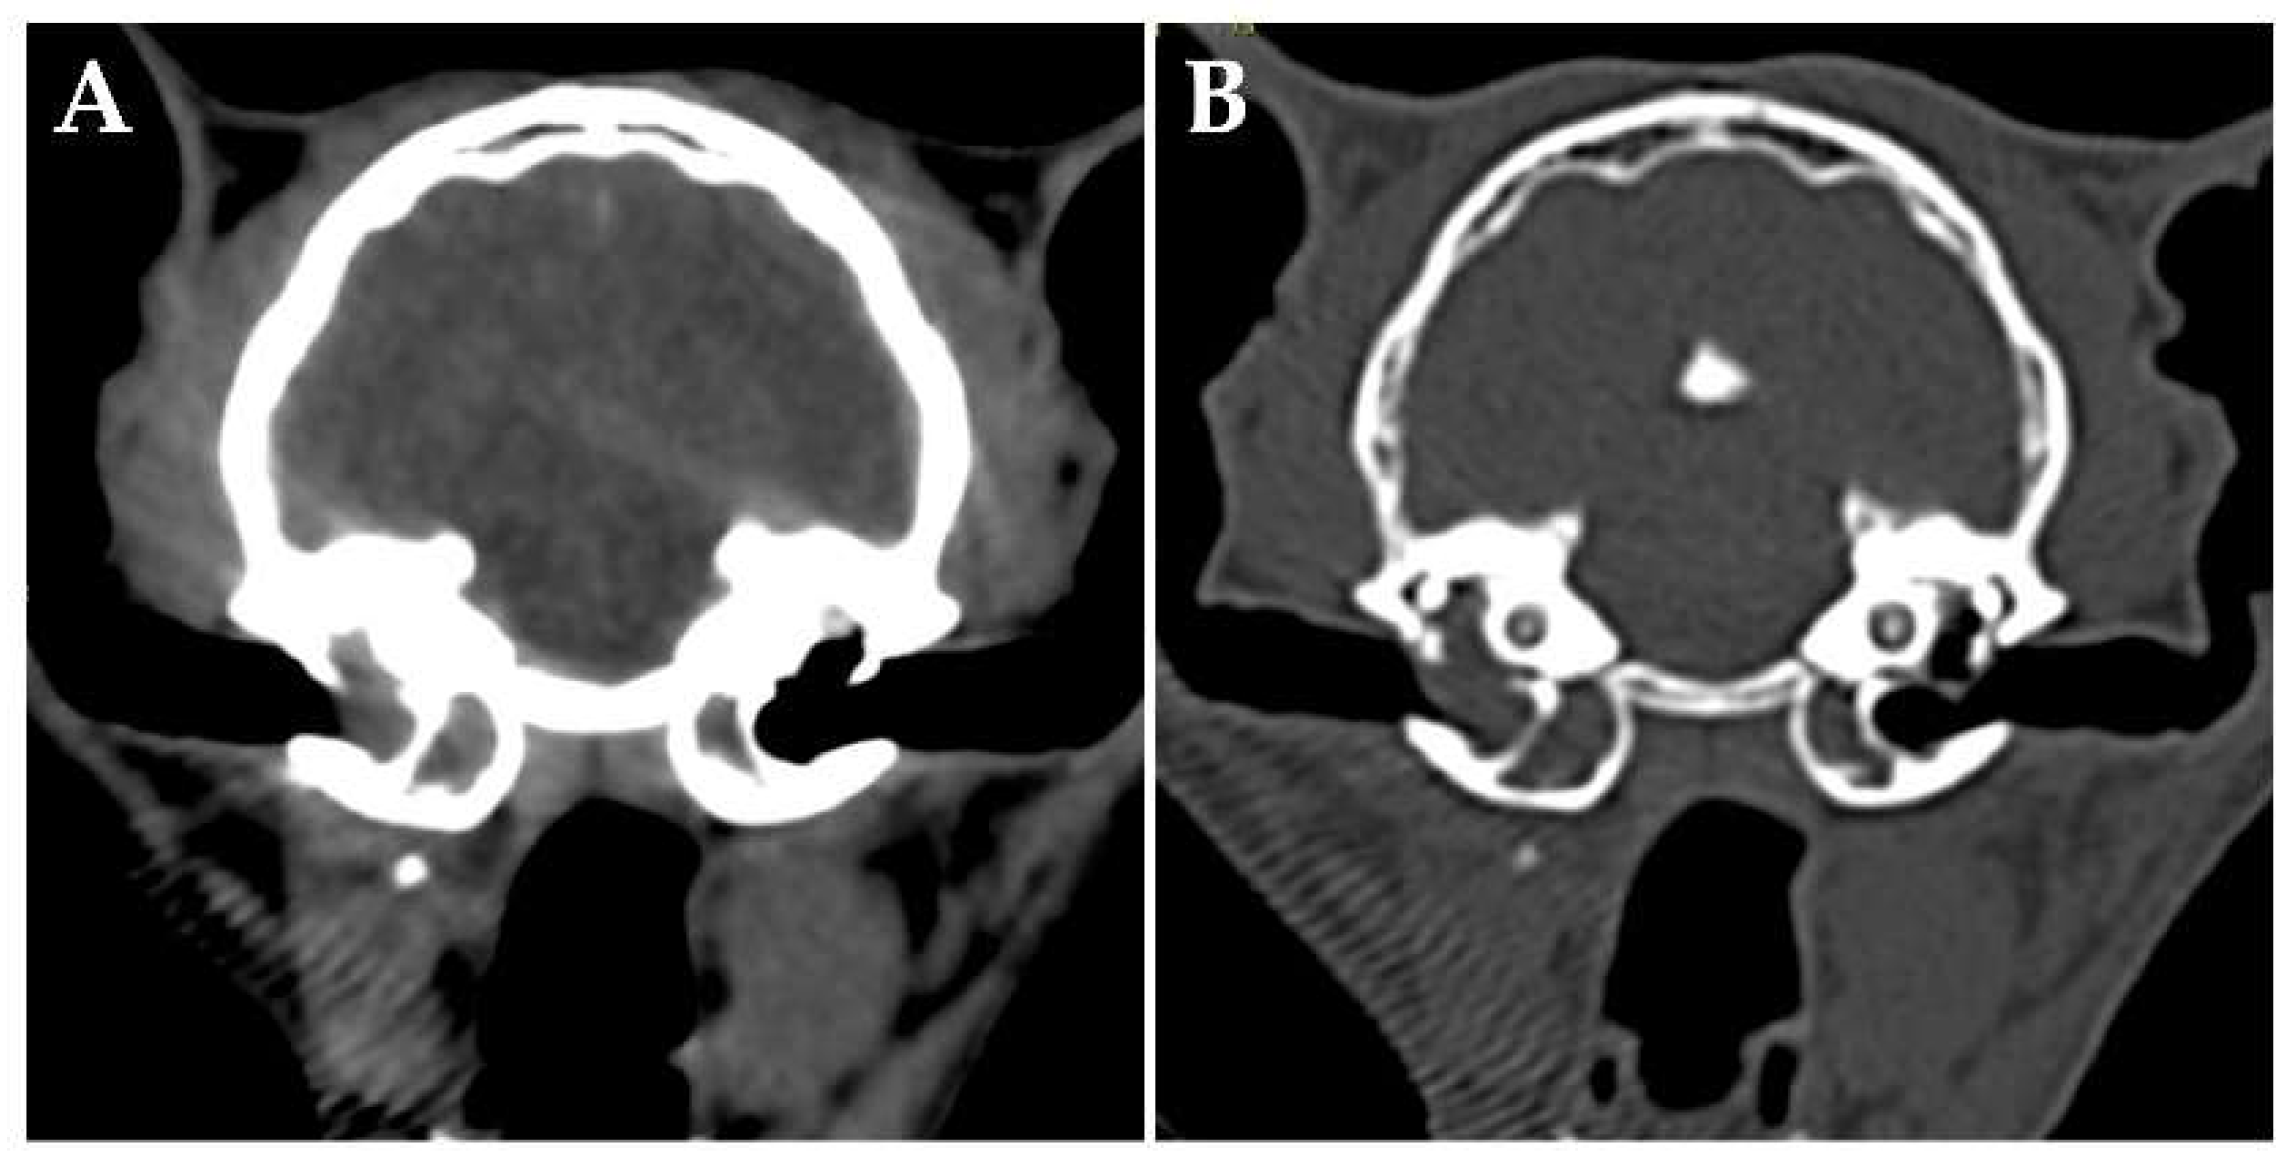

On day 176, the patient had an unstable appetite and nasal obstruction sounds. Intraoral examination revealed a soft palate swelling. Blood tests revealed no particular abnormalities. A contrast-enhanced whole-body CT scan was performed under anesthesia, which revealed unchanged filling of the bilateral tympanic bullas, but no obvious bony abnormalities. A mass lesion with heterogeneously contrast-enhancement was found on the ventral of the right tympanic bulla, which almost completely obstructed the nasopharyngeal region (Figure 4). The right medial retropharyngeal lymph node was contiguous with the ventral lesion of the tympanic bulla and heterogeneously contrast enhanced. Multiple contrast-enhanced mass lesions were noted in the liver (maximum diameter 18 mm). There were no obvious intrathoracic or intra-abdominal organs abnormalities other than the liver. An MRI scan of the head revealed no obvious meningeal lesions and no obvious abnormal findings in the brain. A tentative diagnosis was made that the lymphoma in the right middle ear had spread to the Eustachian tube and formed a mass in the nasopharyngeal region.

Figure 4. Transverse images on day 176. Computed tomography (CT) (A) and magnetic resonance imaging (B) of the head at the level of the middle ear. A mass lesion which is heterogeneously enhanced by contrast media is present in the nasopharyngeal region. the abdomen at the level of the liver, and of the head. In CT image of the abdomen, multiple hypo-attenuating, contrast-enhanced nodules are present in the liver (C: pre-contrast, D: post-contrast).